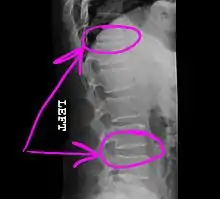

Today, the telestrator is used in a wide variety of applications (from educational, boardroom, church and military presentations to telemedicine conferences), where it can be used by both the near and far ends to annotate precise details of microscopic images or other medical images that are under consultation. The telestrator is also used in courtrooms to communicate details of multimedia images presented to a jury, as was most famously seen during the O. J. Simpson trial in March 1995.[2]

Example of how a telestrator might annotate a medical image shared during a telemedicine session.